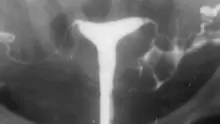

ما هي الاستعدادات المتعلقة بإجراء أشعة الصبغة للرحم؟؟